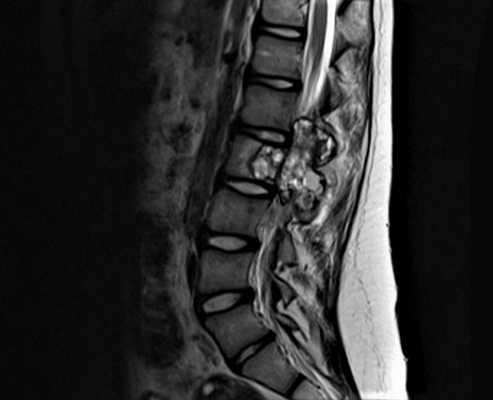

- МРТ

Дополнительно для подтверждения диагноза и оценки состояния межпозвонковых дисков, спинного мозга, мягкотканых структур пациентам может назначаться МРТ. Комплекс этих исследований позволяет правильно оценить степень агрессивности костной кисты позвоночника, а также разработать оптимальную тактику лечения.